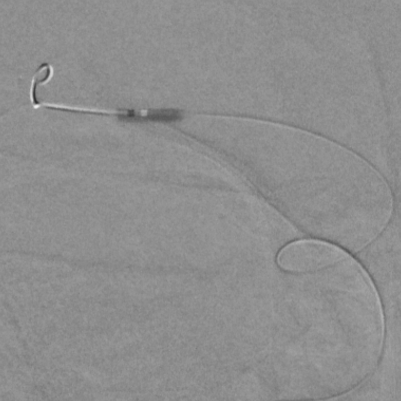

远侧桡动脉入路

准备稍微球扩一下

测量

远端局部球扩

近端局部球扩